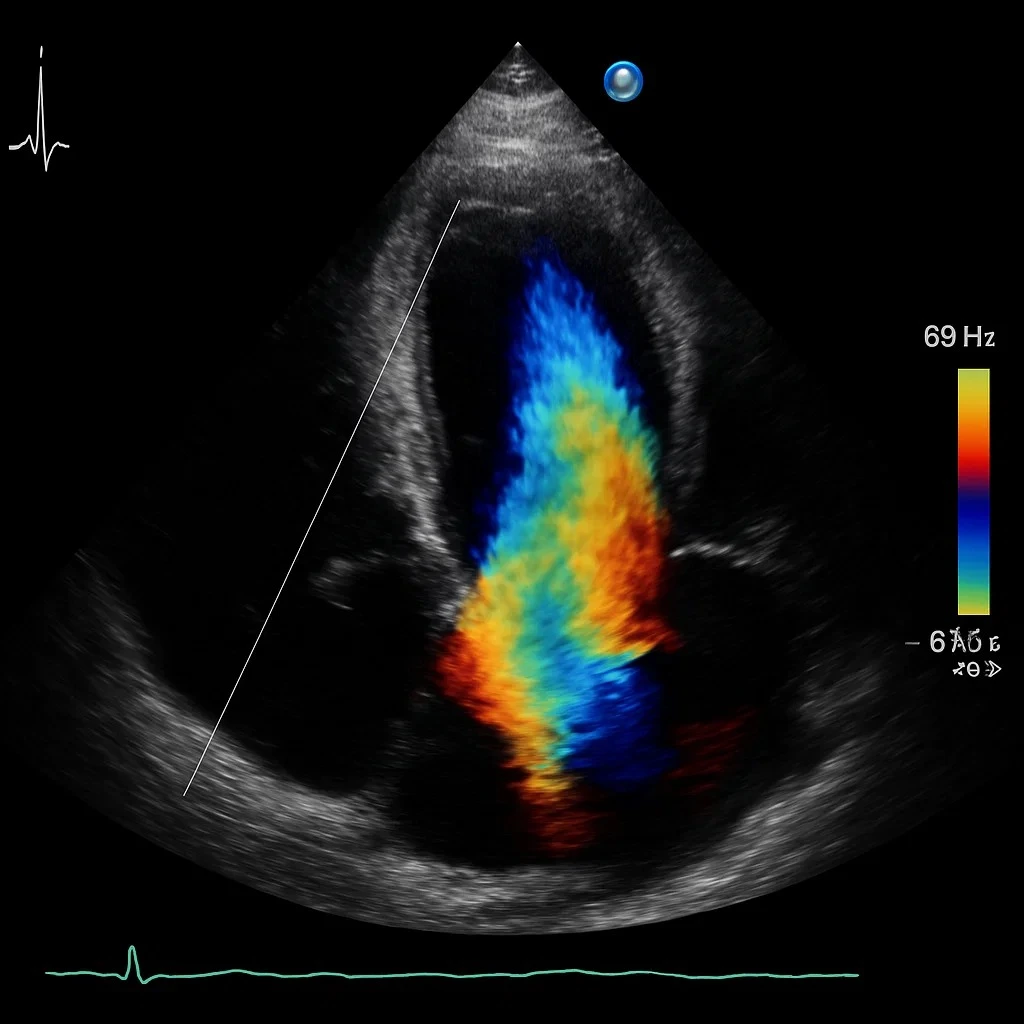

The diagnostic section is equipped with the latest MRI, CT Scan, Ultrasound, Colour Doppler, X-Ray, Pathology Lab, Endoscopy and Colonoscopy, Coronary Angiography, Echocardiography, TMT, NCV, EEG, EMG, Sleep Study, Mammography, DEXA Scan to provide timely and accurate diagnosis to our clinicians.

Siddh Hospital has got cutting edge advanced medical technology to take care of most complex of the diseases. Latest Flat Panel Cath Lab from Siemens, Germany is capable of doing the most difficult Coronary Procedures. The Radiology department has 64 Slice CT Scanner, 4D Ultrasound and Colour Doppler, Digital X-Ray, Mammography, DEXA Scan while the Cardiology Department has the facilities of Echocardiography, Treadmill Test, Holter and ECG. The Hospital has fully modular operation theatres and fully equipped ICU and CCU. Siddh Hospital has inhouse blood bank with component seperator and a dialysis centre.